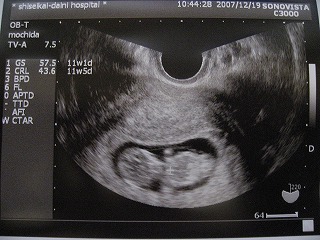

↓写真2枚目:妊娠11週目のわが子は4cm。すっかり頭と胴体と手と足が区別出来てる!

生物って凄いなぁ...。

妊娠11週のわが子